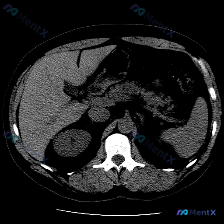

整理了一份很有意思的影像读片案例,一开始容易被提问带偏,仔细看下来其实是一个非常好的“临床思维”训练。 --- 病例基本情况 用户提出的问题是:“图像中描绘的具体异常是什么?脾脏病变”,附带了一幅腹部CT横断面(软组织窗)图像。 关键影像表现 我梳理了一下图像里的核心信息: 1. 脾脏:大小、形态正...

看到一份腹部CT的单幅影像分析,关于脾脏的这个病灶,觉得很有讨论价值,整理一下思路和大家分享。 --- 先看影像给出的客观发现 - 基本情况:单幅腹部CT横断面(层面未全,仅看所示范围) - 阳性表现: 1. 脾脏实质内见一类圆形低密度灶,边界尚清晰,内部密度均匀 2. 病灶CT值近似水样密度 3....

最近看到一份腹部平扫CT的影像资料,主要异常集中在脾脏,整理了一下读片和分析思路,和大家分享。 先整理一下核心影像事实 这是一张腹部CT软组织窗横断面图像,主要发现如下: 1. 肝脏:实质密度尚均匀,未见明确局灶性占位,肝叶比例、血管走行基本正常 2. 脾脏:形态正常,但脾实质内可见一个圆形、边界相...

看到一份很有意思的影像资料,题目直接问“图中的特定异常是什么?脾脏病变”,但仔细读完整份影像分析和临床报告,觉得这里的思维路径特别值得拿出来聊一聊。 先整理一下这份病例的核心影像表现 - 肝脏:形态尚可,实质密度未见明显异常局灶性减低或增高区 - 脾脏:左上腹,形态及大小未见明显增大,实质密度均匀,...

今天看到一个提问很有意思——直接问“脾脏病变”,但把影像资料和分析理了理,发现这里有个很典型的临床认知陷阱,整理出来和大家讨论。 先把完整客观影像信息放前面(别被提问带偏): --- 一、客观影像所见(腹部CT平扫软组织窗) 1. 图像质量:伪影少,软组织对比度好,满足诊断 2. 关键解剖结构: -...